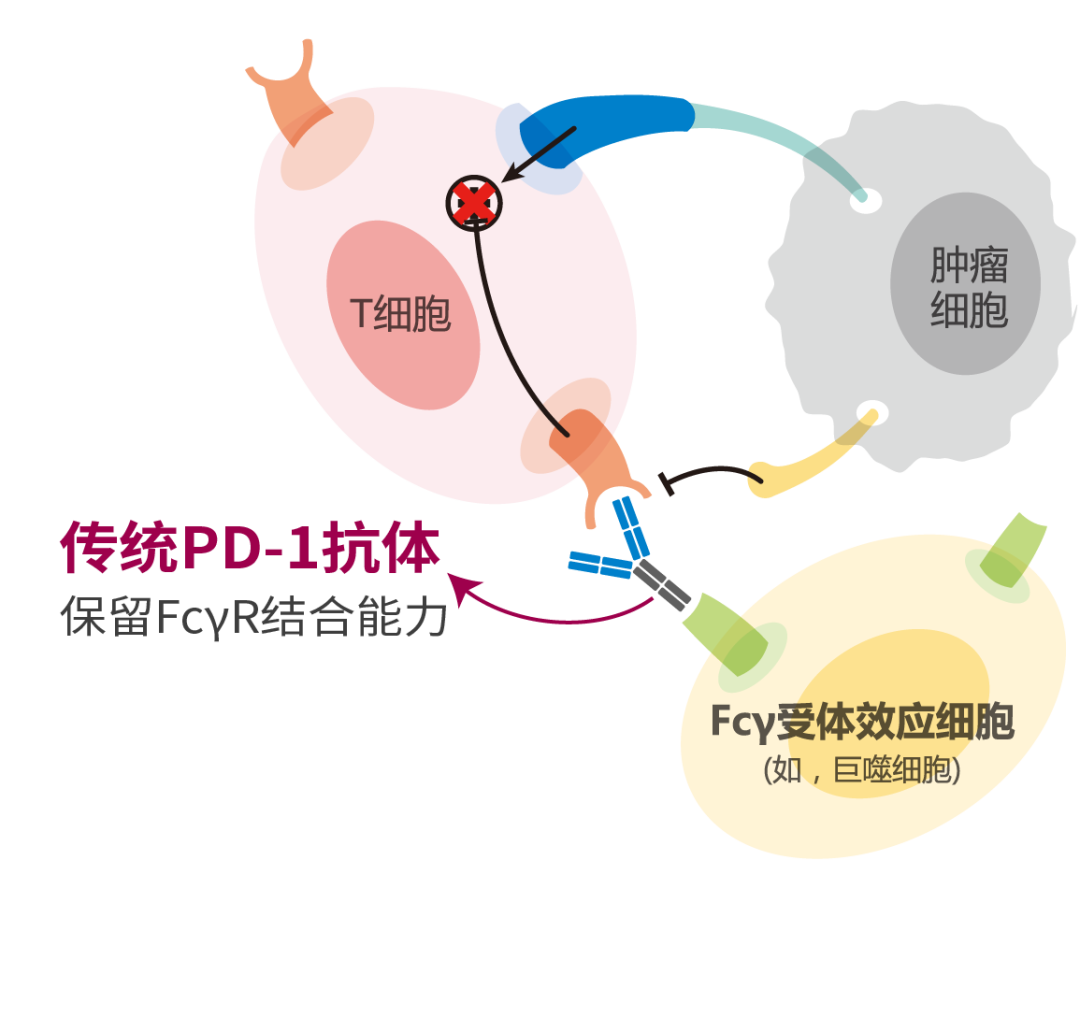

替雷利珠单抗是由我国自主研发的一种新型人源化IgG4型单克隆抗体,其Fc段去除了与巨噬细胞FcγR结合的能力,从而有效避免了巨噬细胞介导的吞噬(ADCP)效应,减少效应T细胞消耗,能够更强地杀伤肿瘤细胞。所以在巨噬细胞数量较多的肿瘤(如肝癌)中具有较优的T细胞激活效应,同时可以避免巨噬细胞引发的不良反应。早期临床研究报道显示,替雷利珠单抗在晚期实体肿瘤患者中普遍具有良好的耐受性和抗肿瘤活性。